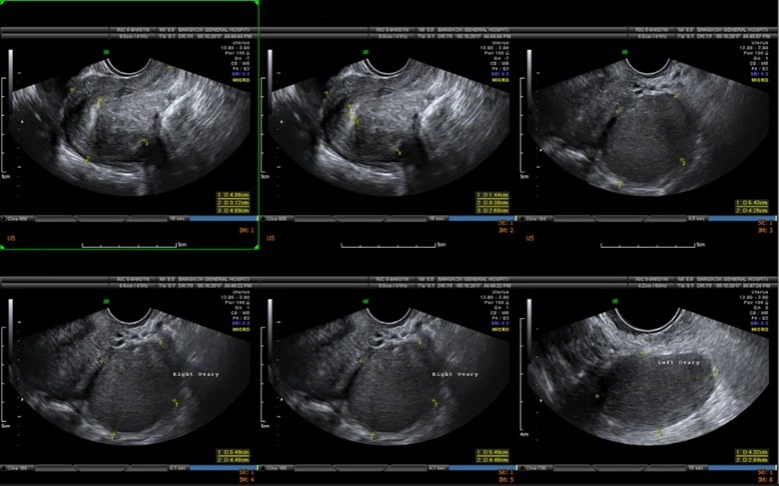

อันดับแรกคือ"เนื้องอกในมดลูก"เป็นโรคที่เกิดในกล้ามเนื้อมดลูก การโตของเนื้องอกอาจโตในโพรงมดลูกหรือโตเป็นก้อนนูนจากมดลูก พบบ่อยในผู้หญิงอายุระหว่าง30-40ปี ส่วนใหญ่ไม่ทราบสาเหตุ ผู้หญิงใน 10 คน มักตรวจพบเนื้องอกมดลูกได้ 3-4 คน ส่วนมากมักจะตรวจเจอโดยบังเอิญ และมีถึง 30 เปอร์เซ็นต์ที่ต้องรับการรักษา อาการที่มาพบแพทย์มักมาด้วยอาการปวดท้องประจำเดือน หรือประจำเดือนมามากกว่าปกติ อาจมีอาการปวดหลังหรือปัสสาวะถี่ร่วมด้วย ผู้ที่ควรต้องเข้ารับการผ่าตัดเนื้องอก มีอาการบ่งชี้ดังนี้ 1.เลือดออกผิดปกติจากช่องคลอด เช่น ประจำเดือนมามากหรือมากะปริบกะปรอย 2.มีอาการปวดท้องมาก 3.เนื้องอกไปกดทับอวัยวะข้างเคียง เช่น กระเพาะปัสสาวะ ทำให้ปัสสาวะบ่อย 4. ตรวจพบเนื้องอกโตเร็วที่ไม่เคยเจอมาก่อน หรือว่าเคยเจอมาก่อนขนาด 1 ซม. พอติดตามอาการสักประมาณ 3-4 เดือน ขนาดของเนื้องอกกลับโตขึ้นอย่างรวดเร็ว 5.เนื้องอกที่สงสัยว่าจะเป็นมะเร็ง

อันดับสอง"โรคซีสต์รังไข่"รังไข่เป็นอวัยวะขนาดเล็กที่อยู่บริเวณด้านข้างปีกมดลูกทั้ง 2 ข้าง ทำหน้าที่ในการสร้างฮอร์โมนต่างๆ ของผู้หญิงให้สมดุล ในทุกๆ เดือนรังไข่จะผลิตไข่ใบเล็กๆ ออกมา โดยไข่จะเคลื่อนจากด้านล่างผ่านท่อนำไข่ เพื่อเตรียมพร้อมผสมกับอสุจิของเพศชาย ส่วนซีสต์มีลักษณะเป็นถุงที่เต็มไปด้วยของเหลวที่สามารถก่อตัวขึ้นได้ในรังไข่ เมื่อเกิดการตกไข่ผิดปกติ จึงทำให้เกิดการคั่งของถุงน้ำในรังไข่ เกิดไข่ไม่ตก เกิดเป็นถุงน้ำขนาดเล็กในรังไข่มีการแบ่งเซลล์ที่ผิดปกติ"ซีสต์ในรังไข่"หลักๆ มี2ชนิด คือ ซีสต์ที่สามารถหายเองได้ กับซีสต์ที่ไม่สามารถหายได้เอง ซึ่งซีสต์ที่หายเองได้ คือซีสต์ที่เกิดขึ้นได้จากฮอร์โมนของผู้หญิงในทุกๆ รอบเดือน และเป็นซีสต์ที่พบได้บ่อยที่สุด ส่วนซีสต์ที่หายเองไม่ได้ และต้องได้รับการผ่าตัด เช่น ช็อกโกแลตซีสต์ เดอร์มอยด์ซีสต์ และอื่นๆ มีทั้งกลุ่มมะเร็ง และไม่ใช่มะเร็ง เป็นต้น

ซีสต์ในรังไข่ที่น่ากลัวคือ"มะเร็ง"เพราะไม่สามารถวินิจฉัยด้วยเพียงแค่การตรวจอัลตร้าซาวด์(ultrasound) การยืนยันการวินิจฉัยโรคเพื่อให้ได้ข้อเท็จจริง คือต้องตัดชิ้นเนื้อไปตรวจด้วยวิธีการผ่าตัดส่องกล้องเท่านั้น สำหรับ"ช็อกโกแลตซีสต์"เป็นซีสต์ที่มีอาการ เช่น ปวดท้องช่วงมีประจำเดือนแบบมากกว่าปกติ ส่วนซีสต์อื่นๆ มักไม่มีอาการ โดยเฉพาะ"มะเร็ง" 80%มักไม่มีอาการ แต่คนไข้มักจะมาพบแพทย์ด้วยอาการท้องบวมอย่างเห็นได้ชัด ท้องอืด แน่นท้อง น้ำหนักไม่ค่อยลง สำหรับอาการปวดท้องน้อยเฉียบพลันนั้น อาจเกิดจากซีสต์รั่วหรือบีบขั้ว ทำให้เกิดอาการปวด บางคนโชคร้ายซีสต์ที่เป็นมะเร็งแตก ส่งผลให้มะเร็งแพร่กระจายลามไปทั่วอวัยวะอื่นๆ ต้องตัดรังไข่ออก หลังผ่าตัดต้องรับการบำบัดด้วยคีโมต่อ

หรือบางคนเป็น"ซีสต์แบบบีบขั้ว"ก็ต้องตัดรังไข่ออกเช่นกัน เพราะเนื้อตายเนื่องจากเลือดไปเลี้ยงไม่ได้ บางคนไม่อยากมีลูกแล้วและไม่อยากกลับมาเป็นซีสต์อีกก็ตัดรังไข่ออก หรือเข้าสู่วัยทองแล้วก็สามารถตัดออกได้ กรณีคนที่ตัดแต่ซีสต์ออก แต่ไม่ได้เอารังไข่ออกก็มีโอกาสกลับมาเป็นซีสต์ได้อีก ซึ่งการรักษาสามารถส่องกล้องผ่าตัดได้เหมือนการรักษาเนื้องอกในมดลูก